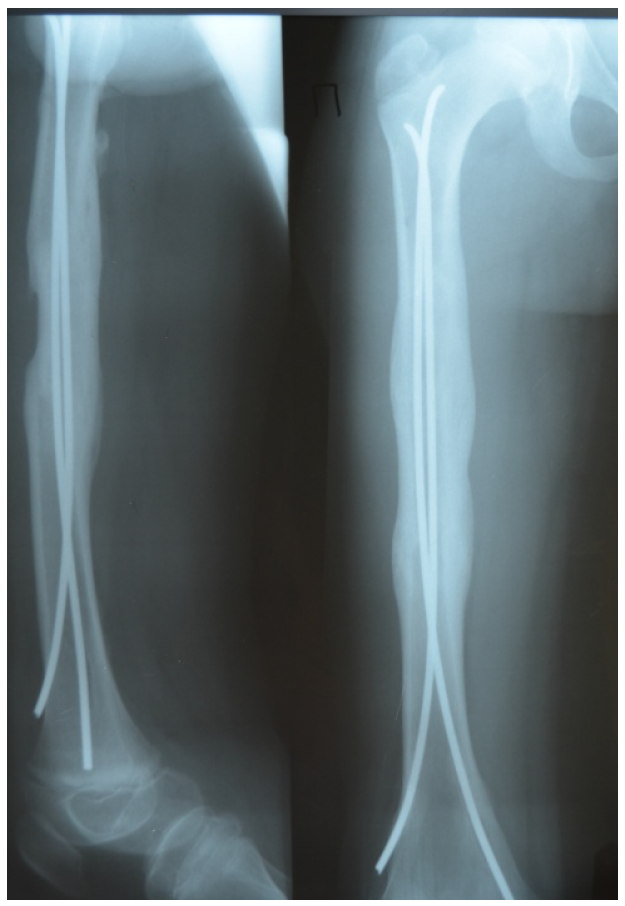

При сочетанной травме конечностей и головы легкой и средней тяжести мы старались проводить хирургические вмешательства в 1-е сутки в рамках противошоковых мероприятий, при компенсированном состоянии больного. Так, у пациента В., 10 лет, при поступлении через 2 часа после ДТП поставлен диагноз сочетанной травмы головы и конечностей: ушиб головного мозга средней степени, перелом ключицы, бедра, большеберцовой кости слева. Выполнен малоинвазивный остеосинтез ключицы, спица оставлена транскутанно, фиксация эластичными титановыми стержнями TEN костей бедра и голени (рис. 5).

Оскольчатый перелом большеберцовой кости потребовал временной иммобилизации гипсовой шиной для стабильности. Подобные мероприятия не только облегчили персоналу уход за больным, но и оптимизировали посттравматический период. Через 3 дня после травмы пациент переведен из реанимационного отделения в обычную палату. Частичная осевая нагрузка разрешена через 2 месяца после травмы, полная – через 3,5. Сроки консолидации соответствовали таковым при одиночном повреждении сегмента. Травматическая болезнь не развилась. Ранняя фиксация отломков существенно уменьшила болевой симптом и привела к ранней нормализации вегетативных функций.

Рис. 5. Больной К., 10 лет. Результат симультантной операции на трех сегментах (ключица, бедро, большеберцовая кость), выполненной через два часа после автодорожной травмы